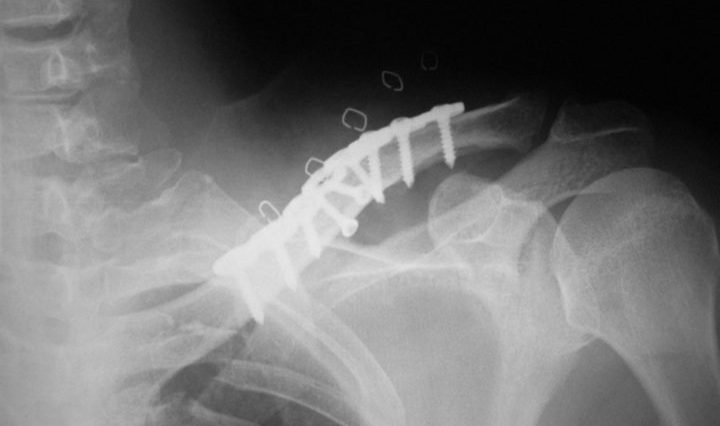

Exploring the Link between Clavicle Fixation Vein Thrombosis and Thoracic Outlet Syndrome